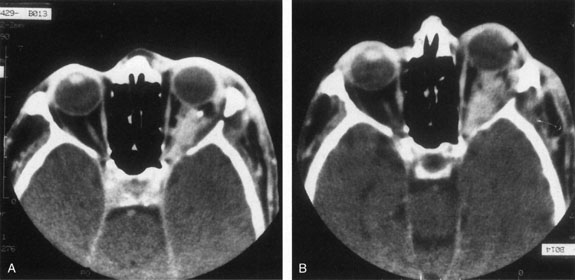

If NFM is suspected, MRI should be ordered of the orbits and brain to exclude noncontiguous intracranial anomalies.93 Magnetic resonance imaging demonstrates the dilated cystic spaces with either a hypointense (lymphatic cyst) or hyperintense (hemorrhagic cyst) signal on T1-weighted images, and a hyperintense signal on T2-weighted images (Fig. 10, A&B).94Layering may be seen within the cysts if there has been a recent hemorrhage leaving unresorbed blood. The CT scans of patients with a deep NFM show low-density, poorly defined masses behind the orbital septum in the extraconal and intraconal spaces, which may indent the globe.3 Calcification within the mass (Fig. 11) and inhomogeneous enhancement of the rim and focal areas within the lesion may be seen that corresponds to abnormal endothelially lined channels.3 Enlargement of the bony orbit can occur, particularly with combined lesions.3,89 If the diagnosis is still unclear, ultrasonography can be performed. A cystic orbital mass is seen on B-scan. A-scan shows features of a solid, cellular tumor: low reflectivity, regular homogeneous internal structure, and marked sound attenuation through the mass.3,89 Standard pulsed Doppler ultrasound confirms no intrinsic flow within the lesions.

Fig. 14. Orbital venous flow malformation. Axial computed tomography scan showing an ill-defined, dense, inhomogeneous orbital lesion with the patient in a supine position (A). Note the phlebolith, which indicates venous stagnation. As the venous flow malformation distends with the patient in the prone position, the lesion enlarges (B). (Courtesy of Dr. John V. Linberg, University of West Virginia, Morgantown, WV)